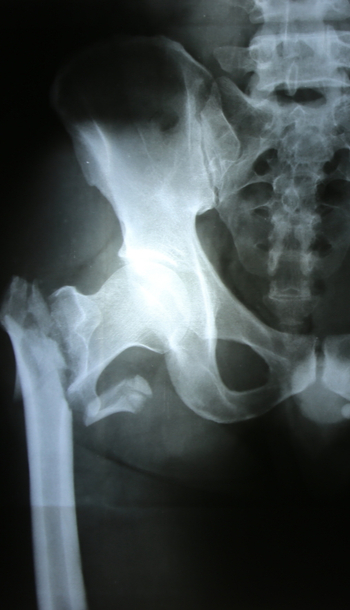

Plan de cuidados: fractura de cadera

En el siguiente caso clínico sobre el Plan de cuidados del paciente con fractura de cadera se mostrarán los cuidados de enfermería a seguir para mejorar y prevenir posibles complicaciones de salud de estos pacientes. Las autoras del caso clínico son Ana Isabel Terriza...